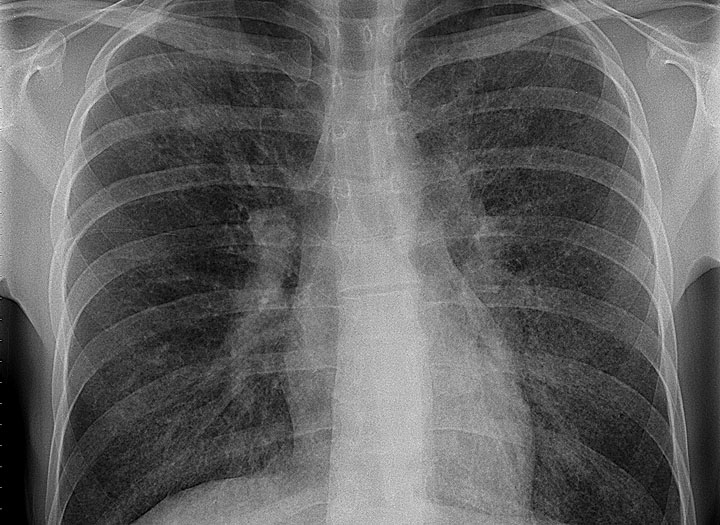

Mniejsza z tą panią. Wykonałem tomografię płuc w wysokiej rozdzielczości. Wyszedł i miód, i cud, na mlecznej szybie ryba z kitem wyszły, przez szybę zaś siateczki, plastry oraz inne, rozmaite obszary. Co do obecności pszczół pewności nie uzyskałem. Się wyroją, się ewentualnie zobaczy – w każdym razie dziś brzęczy we mnie wyraźniej niż wczoraj. A tu podsumowanie badania: “Zmiany w płucach o radiologicznym wzorcu prawdopodobnego UIP o niewielkim nasileniu (15-20%)”. Obraz radiologiczny moich ukochanych acz niedomagających płuc otrzymałem więc niecharakterystyczny, mimo obecności charakterystycznych zmian dla płuc wątpiących. Włókniejących, znaczy. Czyli co robić? Nic. Nadejdą zmiany, się uwidocznią, za charakterystykę zmiany złapiemy, odpowiednio przesłuchamy.